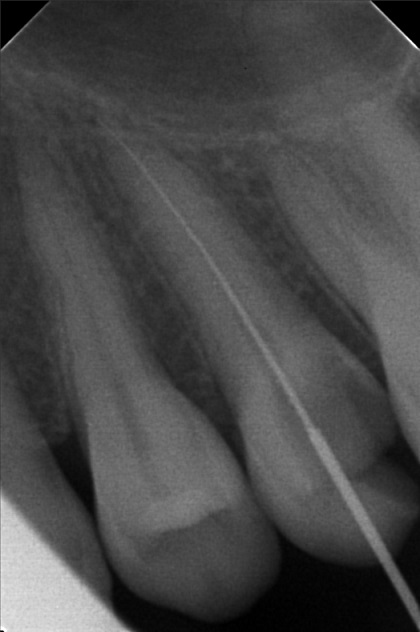

Edit Record Check our patient data records. Add patient information Patient Info Profile picture Last Name First Name Middle Name Birthdate Age Street Barangay City Country Zip Code Contact number Email Procedure 10/01/22 - OP(L); RESTO #26 ; #48; ACCESS #25 Scouting file #10 20mm; Closed with formocresol; Prescribed Tramadol +Paracetamol 325mg 10/08/22 - FILE 35 -19mm, CLOSED W/ CAMPHENOL; RESTO #22(LINGUAL), #47 (O & BUCCAL PIT) 10/15/22 - FILE 35 - 19mm, CLOSED W/ FORMECRESOL, RESTO #18(OB), #27, #28 10/22/22 - OBTURATE, FINAL RESTO#25, RESTO #16 (OL), #38 (O) File jamjam.jpg File 2 jamjam_02.jpg File 3 jamjam_03.jpg File 4 jamjam_04.jpg File 5 jamjam_05.jpg File 6 File 7 File 8 File 9 File 10 File 11 File 12 File 13 File 14 File 15 File 16 File 17 File 18 File 19 File 20 Retain Record Retain Record Yes No Save Your Changes